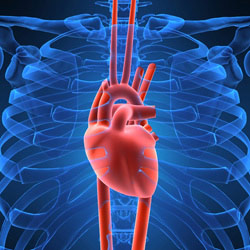

Powerful Pump

In under a minute, your heart can pump blood to every cell in your body. And over the course of a day, about 100,000 heart beats shuttle (穿梭往返运输) 2,000 gallons of oxygen-rich blood many times through about 60,000 miles of branching blood vessels that link together the cells of our organs and body parts. That's a hefty (重的) job for a fist-sized muscle.

Photo Credit: National Heart, Lung and Blood institute